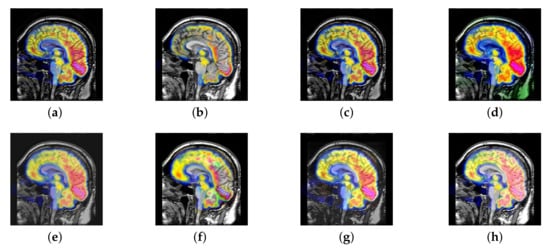

In this section, there are four multi-modal image sets and each set is consist of MRI image and SPECT image that are corresponding to the sanme location slice of the brain as shown in Figure 7. Among them, Figure 7e,f are captured from patients who have suffered a subacute stroke. Figure 7a–d,g,h are captured from patients who have brain tumor. The fused images with different fusion methods based on DTCWT, NSCT, GFF, LPSR, IGM, DDcGAN, FusionCNN, and the proposed methods are shown in Figure 8, Figure 9, Figure 10 and Figure 11. It can be seen that the fused images obtained by LPSR and FusionCNN algorithm have serious color distortion. Based on DTCWT and NSCT algorithm, the fusion image structure information is not obvious. The fused images obtained by GFF and IGM algorithm contain almost no color information, which is not conducive for doctors to make correct diagnosis. The image obtained by the DDcGAN algorithm saves the color information in the SPECT to a great extent; however, the brightness of the fused image is too large, which causes the image to have no sense of hierarchy and the contrast to decrease. By comparing with other algorithms, we find that our algorithm has good color retention effect, clear structure information, moderate brightness, and no artifacts.

Figure 8.

Fused medical images obtained by different algorithms (Figure 7a,b): (a) dual tree complex wavelet transform (DTCWT), (b) guided filtering fusion (GFF), (c) non-subsampled contourlet transform (NSCT), (d) Laplacian pyramid sparse representation (LPSR), (e) internal generative mechanism (IGM), (f) Fusion convolutional neural network based (FusionCNN), (g) dual-discriminator conditional generative adversarial network based (DDcGAN), and (h) FusionNet.

Figure 9.

Fused medical images obtained by different algorithms (Figure 7c,d): (a) DTCWT, (b) GFF, (c) NSCT, (d) LPSR, (e) IGM, (f) FusionCNN, (g) DDcGAN, and (h) FusionNet.

Figure 10.

Fused medical images obtained by different algorithms (Figure 7e,f): (a) DTCWT, (b) GFF, (c) NSCT, (d) LPSR, (e) IGM, (f) FusionCNN, (g) DDcGAN, and (h) FusionNet.

Figure 11.

Fused medical images obtained by different algorithms (Figure 7g,h): (a) DTCWT, (b) GFF, (c) NSCT, (d) LPSR, (e) IGM, (f) FusionCNN, (g) DDcGAN, and (h) FusionNet.